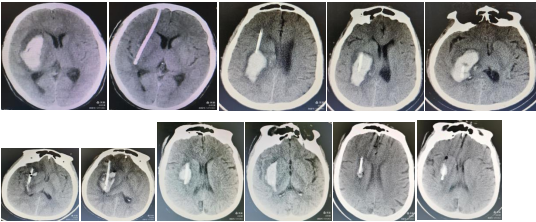

2020年12月10日,在巨清主任的带领下,神经医学科正式开科,2个多月的时间里,成功开展多例脑动脉瘤破裂开颅夹闭、多发脑动脉瘤开颅夹闭、脑动静脉畸形显微切除、脑膜瘤开颅显微切除术、高血压脑出血开颅显微镜下经侧裂岛叶血肿清除、高血压脑出血微创软通穿刺引流及多例外伤急性硬膜外血肿、急性硬膜下血肿开颅血肿清除术。神经医学科的成立及开展相关手术填补了我院在神经外科领域医疗技术的空白,是医院“技术强院”开展新技术、新业务浪潮中具体表现,真正做到大病不出区,为广大辖区居民的健康提供了强有力的保障! 神经医学科特殊病例展示1.高血压脑出血软通道精准定位单管穿刺治疗2.复杂危重高血压脑出血多管齐下软通道技术,术后一周余大量脑出血脑室出血已经被引流,脑室系统恢复正常3.前颅窝底硬脑膜动静脉瘘DSA造影(行开颅显微手术)4.三叉神经痛微血管减压手术5.微创血管内介入床突旁未破裂动脉瘤栓塞术6.镰旁巨大脑膜瘤、术前切口、手术标本大脑中动脉分叉部动脉瘤夹闭术四脑室髓母细胞瘤手术体位四脑室髓母细胞瘤术前核磁共振成像神经内镜下经鼻蝶入路垂体瘤切除术中三叉神经痛微血管减压术中责任血管(复杂性)三叉神经痛血管减压术中发现责任血管为静脉(少见)血泡样动脉瘤术中夹闭胸段脊髓神经鞘瘤术后半椎板脊突复位胸段脊髓神经鞘瘤术前核磁共振成像

近日,我院神经医学科收治了一例颅内破裂动脉瘤女患者,黄女士的起始症状突发头颈部疼痛伴右眼睑下垂,黄女士的女儿对接诊医生说:“我妈妈突发头痛、右眼睁不开已经6天了,去了省内大三甲医院就诊,但是要排队等做检查,没得到及时治疗,今天她的头痛越来越严重,吓得我们赶紧叫救护车送过来了。” 凶险 脑内藏了一个动脉瘤番禺二院急诊科接诊后,值班医生考虑到脑出血的可能性,立即通知神经医学科会诊,开通危重症绿色通道,15分钟后放射科发来CTA报告,提示蛛网膜下腔出血,右侧颈内动脉后交通动脉瘤。这个结果对于黄女士来说,犹如晴天霹雳,“没想到我脑子里居然藏着一枚"定时炸弹"!太可怕了,幸好你们检查出来了。”入院后急行头颅CTA检查:右侧颈内动脉交通段一囊状凸起,5*9mm,瘤体指向外后方。关怀 保护外观 留住秀发黄女士与家属商议后,决定马上住院手术。虽然手术势在必行,但一想到要把头发剃光、头部还会留下一道触目惊心的伤疤,她就感到脊背发凉。“医生,一定要在头上开个大洞吗?有没有其他办法呀?”黄女士担忧地问道。巨清主任经过充分、缜密的评估,最后决定为黄女士实施经眉毛内微创切口,锁孔下手术。他认为,手术除了要成功处理病灶,也要充分考虑到患者的心理承受能力,保护患者的外观。 手术切口设计:右侧眉毛内2.0cm切口。 精准 眉弓切口2厘米巧拆“炸弹”完善各项术前准备后,在手术麻醉科的紧密配合下,神经医学科巨清主任团队开始手术。手术在全麻下进行,皮肤切口定于眉毛中,长度仅2厘米左右,开颅后形成的骨窗2厘米左右。手术进行得非常顺利,安全拆除“炸弹”,比传统手术方式创伤小,而且节省了一大半的时间,黄女士麻醉复苏后,对答切题,四肢活动正常。术后第二天,头痛症状明显好转,原先睁不开的眼睛也睁开了,更令她高兴的是,一头秀发真的是“毫发无损”。不由得赞叹在番禺二院会得到这么优质的治疗和护理!手术切口皮内美容缝合。 术后2小时复查头颅CT,无新发出血、脑梗塞发生。巨主任介绍说,当前神经外科的趋势,是朝着微创、创伤小、恢复快的理念在转变,通过最小的创伤获得最佳的疗效是神经外科医师长期追求的目标。经眉弓的锁孔手术将切口隐藏在眉毛中,切口小、术中出血少,患者术后的恢复也很快,真正达到了微创、美容的效果。作为微创手术的经典,经眉弓的锁孔手术应用范围非常广泛,不仅可以夹闭颅内多个部位的脑动脉瘤,而且还可以切除前颅底、鞍区的肿瘤等。  巨清主任指导黄女士进行功能锻炼。